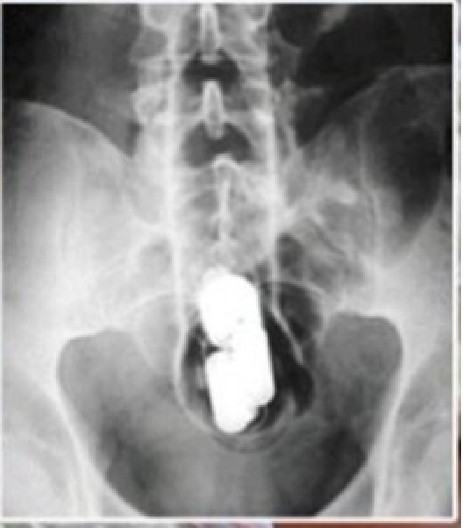

Kao jedan od ključnih dokaza na sudu poslužio je rezultat ginekološkog pregleda i rendgenski snimak stomaka uhapšene na kojem se videlo da je heroin upakovala u prezervativ, a zatim ga gurnula u vaginu.

Box: Image

„Dovitljiva“ dilerka uhapšena je u februaru 2010. godine.

-Policija je sumnjala da je Olga mesecima na taj način prenosila drogu iz Beograda u Zrenjanin. Kad je privedena, kod nje nije ništa pronađeno. Međutim, policajci su je poslali na  ginekološki pregled u bolnicu „Dr Đorđe Jovanović“. Kad je legla na sto, ginekolog je imao šta da vidi. Iz njene vagine izvadio je prezervativ s tri kesice heroina- pisali smo tada a saznali smo u zrenjaninskom Višem sudu.

Posle merenja utvrđeno je da je droga bila teška 12 grama.